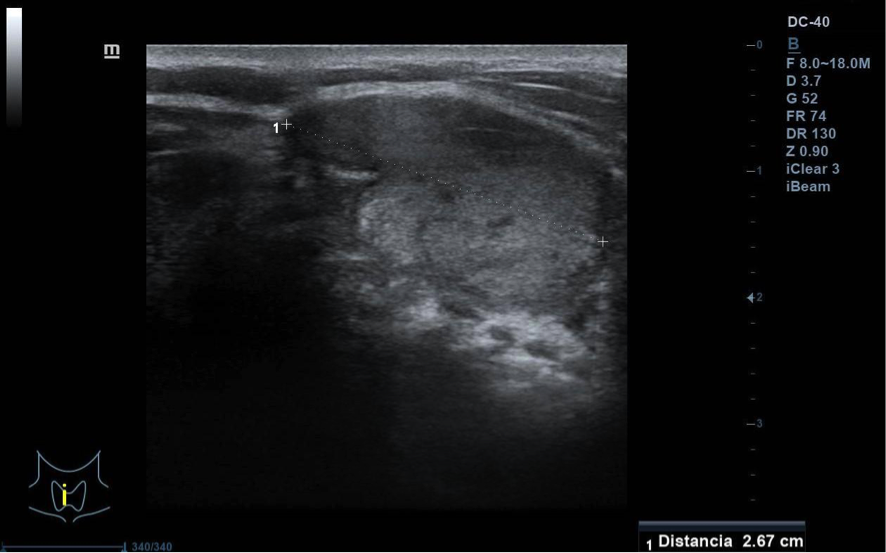

Se visualiza nódulo tiroideo en la unión del istmo con lóbulo tiroideo derecho, sólido, con cierta heterogenicidad, halo grueso anecogénico. Una zona del borde irregular, con mayor señal Doppler y de crecimiento excéntrico. Mide de diámetro máximo 25 x 20 mm. Adenopatías no patológicas.